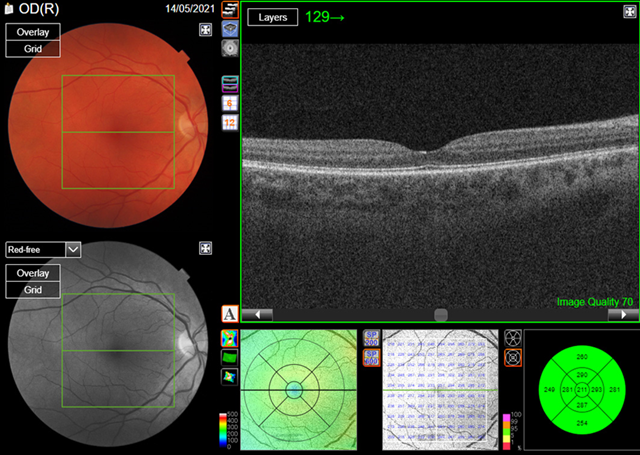

Optical

coherence tomography (oct) is a non-invasive imaging modality that uses

low-coherence light to capture micrometer resolution images of the retina.

Using the information obtained, two and three dimensional images of the retina

are formed which the clinician can use to give an indication of retinal/ rpe

health. The case study patient’s macula oct scans were normal (figures 3a,3b).

(a) Right eye

(a) Left eye

Figure

3.

Optical coherence tomography

(oct)